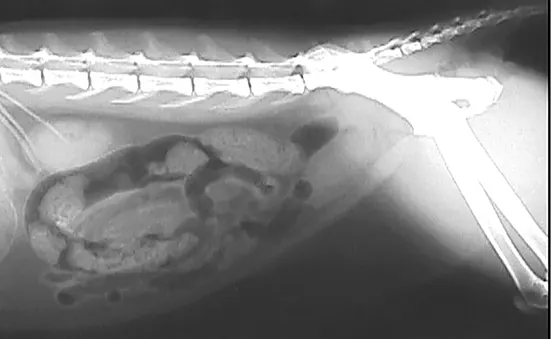

Abdominal radiography and ultrasonography were conducted. Abdominal radiography revealed no abnormalities (Figure 1); ultrasonography revealed 2 small urocystoliths (Figure 2). Medical dissolution was not attempted because the uroliths were not believed to be composed of struvite due to their radiolucency, lack of crystalluria, and aciduria. Because the patient was a male cat, no attempt was made to retrieve the urolith by voiding urohydropropulsion. Percutaneous cystolithotomy1 (Figure 3) was performed. Urocystoliths (Figure 4) were removed and submitted for quantitative analysis.

FIGURE 1

Lateral abdominal radiograph of patient